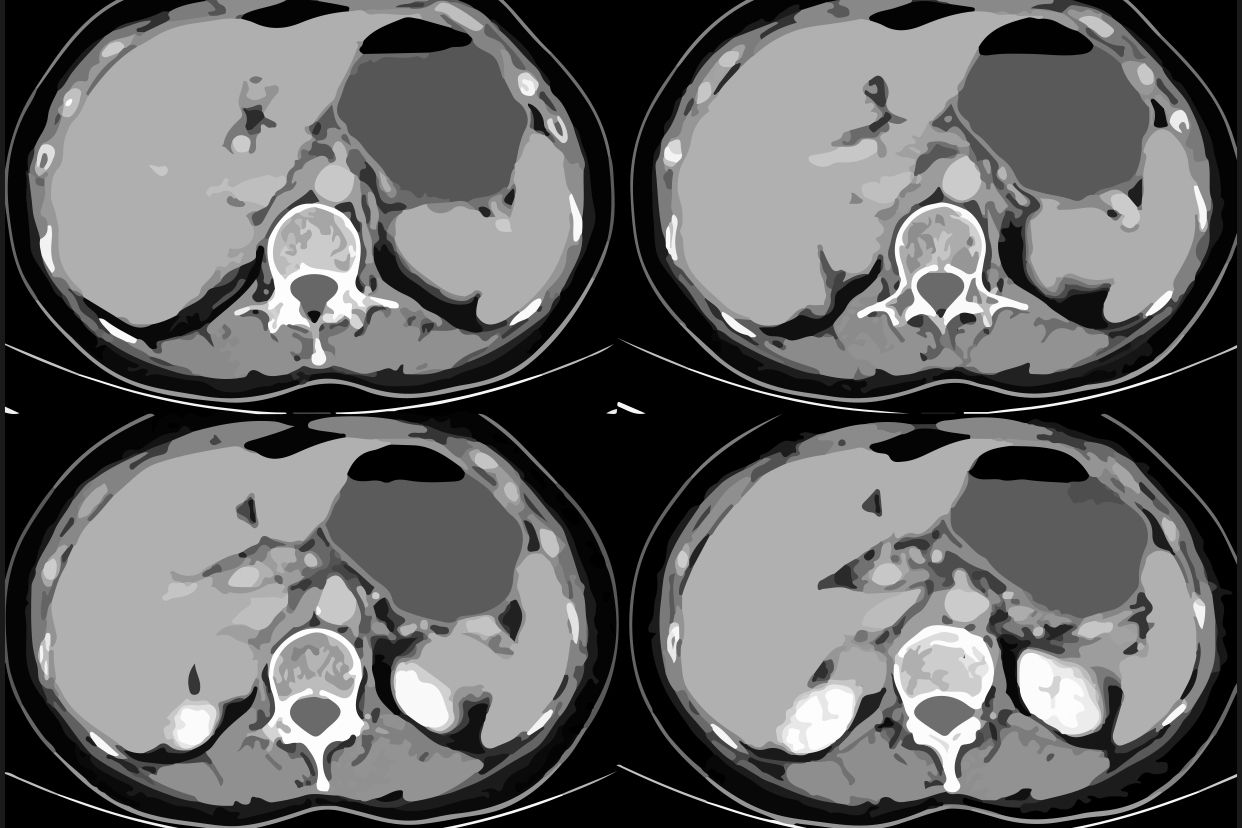

膀胱常见疾病有膀胱炎症、膀胱肿瘤和膀胱结石等。